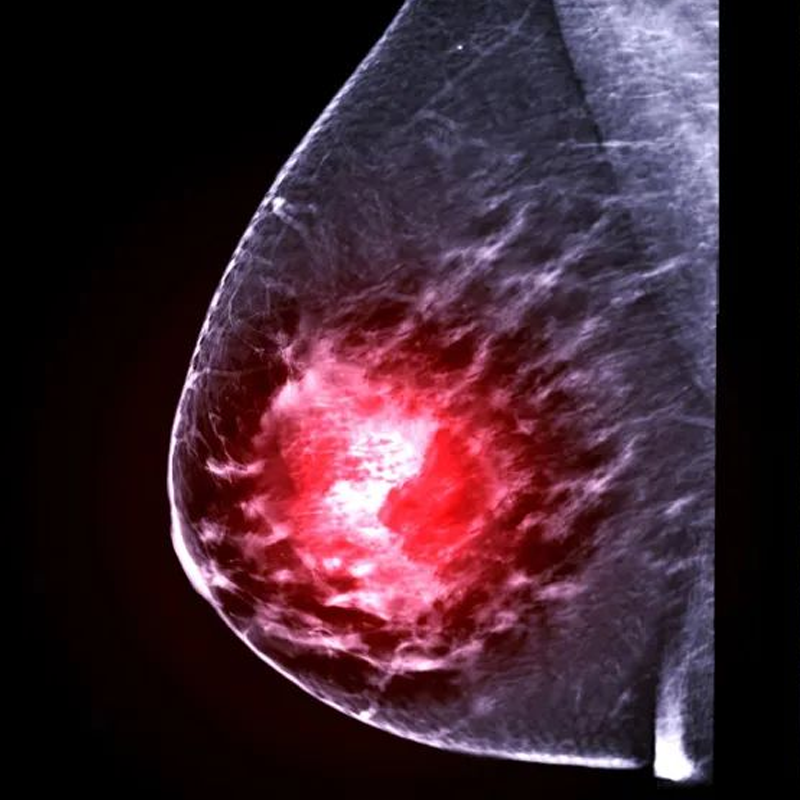

Abnormal Lumps

Are you troubled by these conditions?

- Lymph node

- Pulmonary nodule

- Thyroid nodule

- Chest nodule